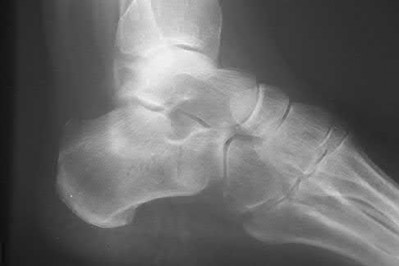

A 34-year-old male sustains the closed injury seen in Figure A as a result of a high-speed motor vehicle collision. What is the most appropriate next step in treatment?

The radiograph shows a comminuted pilon fracture, which is associated with high-energy trauma and significant soft tissue injury. The tested concept here is the importance of avoiding definitive reduction and fixation of this high-energy injury, which has been shown to be associated with an increased risk of wound complications and deep infections (as compared to staged treatment with usage of a spanning external fixator).

Patterson et al. reviewed 23 consecutive patients with comminuted distal tibia fractures. They showed 0% infections or wound-healing problems in their patient population treated with a two-staged protocol. Their protocol involved fibula fixation with an intramedullary implant and application of a medial external fixator to to regain length and restore anatomic alignment. Reevaluation of the limb occurred ten to fourteen days later for definitive fixation.

Sirkin et al. retrospectively reviewed 40 closed and 17 open pilon fractures (AO types 43A-C) that were treated with staged surgical management (avg. time from ext. fix. to formal reconstruction was 14 days (range 4 to 31) They reported 17% post-operative wound complication in the closed group and 11% post-operative wound complication in the open group (Gustilo Type I-III). They suggest the technique was successful in both closed and open pilon fractures.